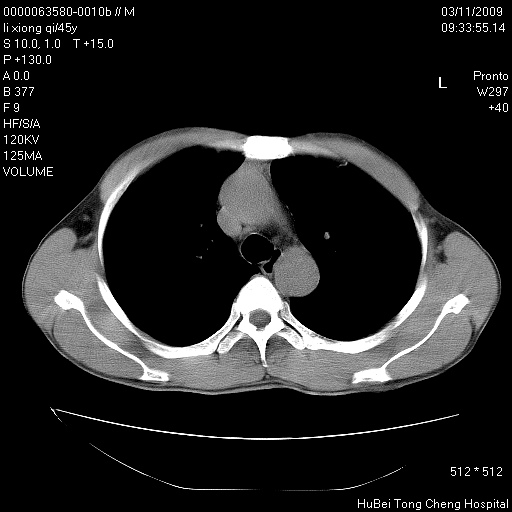

患者 男,45岁。胸痛,咳嗽伴痰中带血1月余。

临床诊断:肺结核?

胸部ct轴位平扫(层厚10mm,螺距1.5,重建间隔10mm),图像如下:

考虑肝癌肺转移